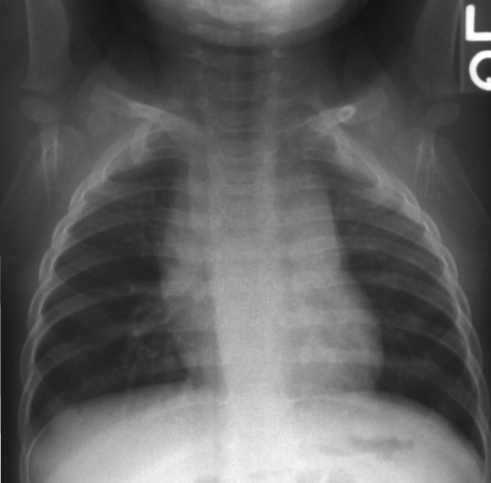

A 7-year-old girl is brought to a local clinic by her parents, who report a sudden onset of severe sore throat and difficulty swallowing starting a few hours ago. Her symptoms have progressed rapidly, and she now struggles to breathe and is visibly distressed. Her immunization records are up-to-date, including all recommended childhood vaccinations. On examination, her temperature is 39.8°C, heart rate is 150/min, respiratory rate is 32/min, and oxygen saturation is 93% on room air. She appears anxious, is drooling, and is leaning forward in a tripod position, refusing to lie flat. Her voice is muffled, and she resists any attempt to inspect her oral cavity. There is no cough or hoarseness. Laboratory findings are pending. Based on this presentation, what is the most likely diagnosis and the immediate critical management step?